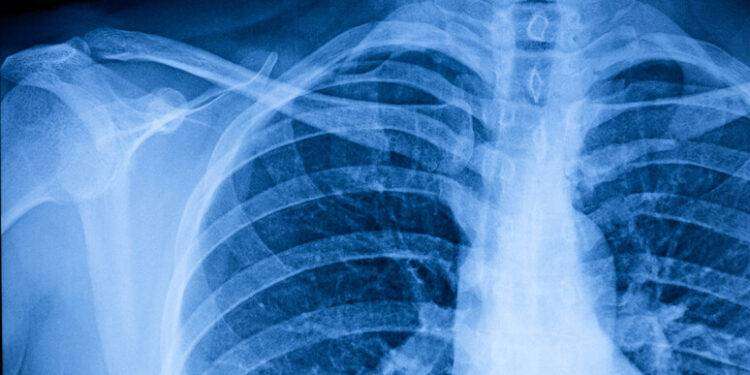

Non solo rughe: l’Intelligenza artificiale sembra in grado di stimare l’età anche dal torace.

A indicarlo è l’algoritmo messo a punto nell’Università Metropolitana di Osaka, in Giappone, che in un articolo pubblicato sulla rivista The Lancet Healthy Longevity dimostrano che le radiografie del torace possono essere usate per stimare il modo accurato l’età cronologica, ossia il tempo trascorso dalla nascita, e soprattutto per identificare i primi segnali di malattie croniche come l’ipertensione.

Una delle più potenti applicazioni degli algoritmi di IA è nella capacità di analizzare milioni e milioni di dati, cercando di identificare schemi impossibili da notare per l’occhio umano, come mettere in relazione impercettibili variazioni della voce e possibili patologie della gola. Sono schemi che possono essere trovati in molte analisi mediche, come le radiografie. Ed è analizzando ben 67.099 radiografie del torace di 36.051 individui sani sottoposti a controlli sanitari in tre strutture mediche. il sistema di IA sviluppato dai ricercatori giapponesi è stato in grado di stimare l’età cronologica dei pazienti, ossia il tempo effettivamente trascorso dalla nascita, con un coefficiente di correlazione di 0,95, praticamente con un altissimo livello di precisione.

Dati da cui la IA ha mostrato anche un’altissima capacità nell’individuazione precoce dello sviluppo di malattie croniche che interessano il torace in vario modo, come ipertensione, iperuricemia e broncopneumopatia cronica ostruttiva. “L’età cronologica è uno dei fattori più critici in medicina”, ha affermato Yasuhito Mitsuyama, uno degli autori dello studio. “I nostri risultati – ha aggiunto – suggeriscono che l’età apparente basata sulla radiografia del torace può riflettere accuratamente le condizioni di salute oltre l’età cronologica. Il nostro obiettivo è sviluppare ulteriormente questa ricerca e applicarla per stimare la gravità delle malattie croniche, prevedere l’aspettativa di vita e prevedere possibili complicanze chirurgiche”.